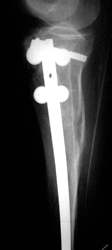

Tibiakopffraktur mit Tibiaschaftfraktur. Geschlossene Nagelung. Nach 3 Wochen volle Belastung. Die rechten zwei Röntgenbilder zeigen den Befund nach einem Jahr.